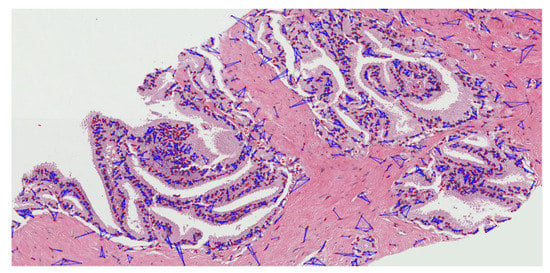

The MST cluster analysis method was applied on the PCa tissue samples of dataset 1 and dataset 2, and the visualization results of intra- and inter-cluster MST are shown in Figure 12. From the following figure, we can analyze that the structure and shape of the clusters in each grade are different from each other. It is quite challenging for researchers and doctors to analyze the microscopic biopsy images of PCa and identify suitable biomarkers compared to other common cancers.

Figure 12.

The visualization of intra- and inter-cluster MST graphs. (a–c) The intra-cluster MST of grade 3, grade 4, and grade 5, respectively. (d–f) The inter-cluster MST was generated from a, b, and c, respectively. The dotted red circle indicates the cluster of cell nuclei. Different color lines in a-c and d-f indicate intra- and inter-clusters, respectively.

The gold standard for the diagnosis of prostate cancer is a pathologist’s evaluation of prostate tissue. To potentially assist pathologists, DL-based cancer detection systems have been developed. Many of the state-of-the-art models are patch-based convolutional neural networks. Patch-based systems typically require detailed, pixel-level annotations for effective training. However, such annotations are seldom readily available in contrast to the clinical reports of pathologists, which contain slide-level labels. Our study sliced annotated and graded images from the pathologist, and we use an MST algorithm to perform cluster analysis and extract significant information for AI classification. The proliferation and cluster structure of cell nuclei, as shown in Appendix A, Figure A4 (Gleason pattern 3), Figure A5 (Gleason pattern 4), and Figure A6 (Gleason pattern 5), will help the pathologist to identify, classify, and grade more precisely the Gleason score assignment in the light of heterogeneity and variability.